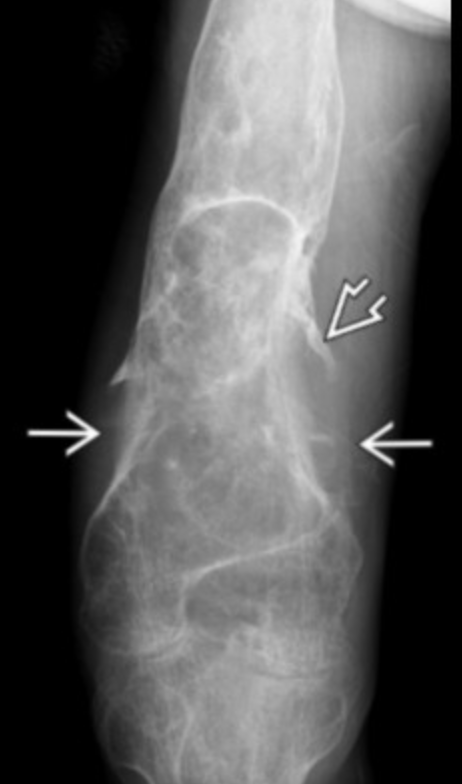

Neuropathic Arthropathy

• Looks like nonspecific destruction of the bone/joint

• Should get spine/brain MR if you see this

• Commonly have syrinx